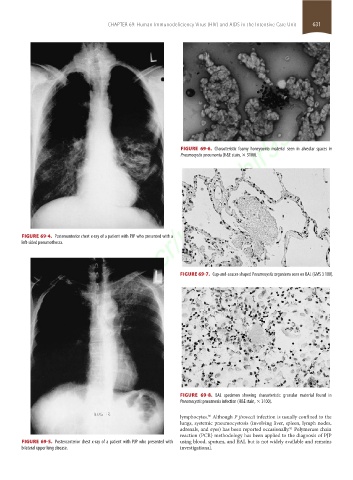

FIGURE 69-6. Characteristic foamy honeycomb material seen in alveolar spaces in

Pneumocystis pneumonia (H&E stain, × 3100).

FIGURE 69-4. Posteroanterior chest x-ray of a patient with PJP who presented with a

left-sided pneumothorax.

FIGURE 69-7. Cup-and-saucer-shaped Pneumocystis organisms seen on BAL (GMS 3 100).

FIGURE 69-8. BAL specimen showing characteristic granular material found in

Pneumocystis pneumonia infection (H&E stain, × 3100).

FIGURE 69-5. Posteroanterior chest x-ray of a patient with PJP who presented with using blood, sputum, and BAL but is not widely available and remains

bilateral upper lung disease. investigational.